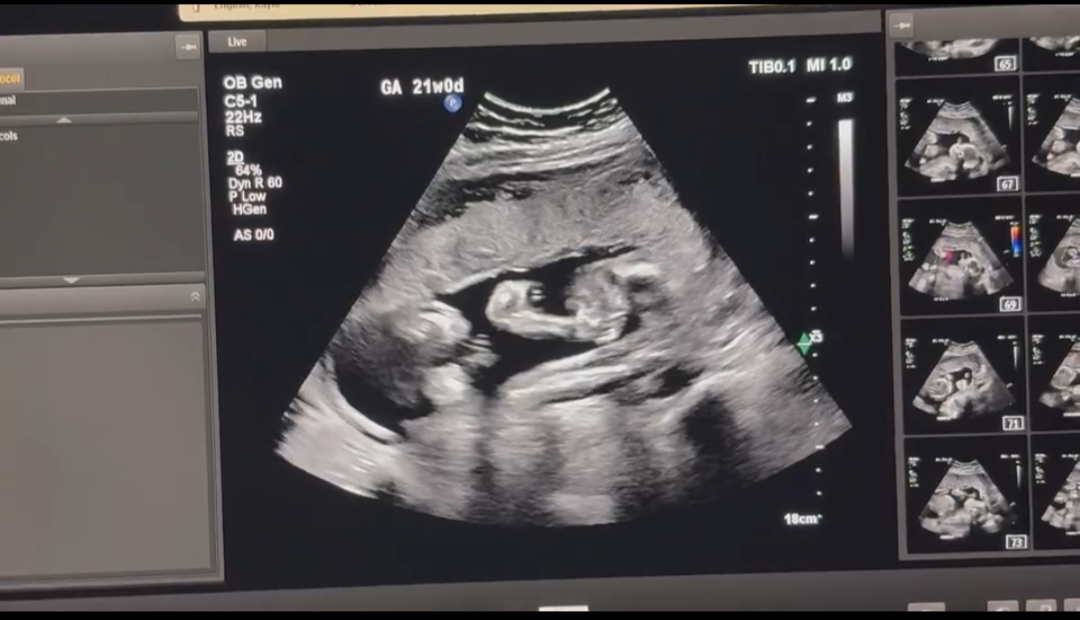

Week 21

Week 21 out of 40 of Pregnancy!

We got to see baby again! The anatomy scan was fun for mom and dad, but the technician had a hard time getting good photos of baby because baby kept jumping around! Baby is measuring “perfectly” and has both arms and legs, and a healthy heartbeat.